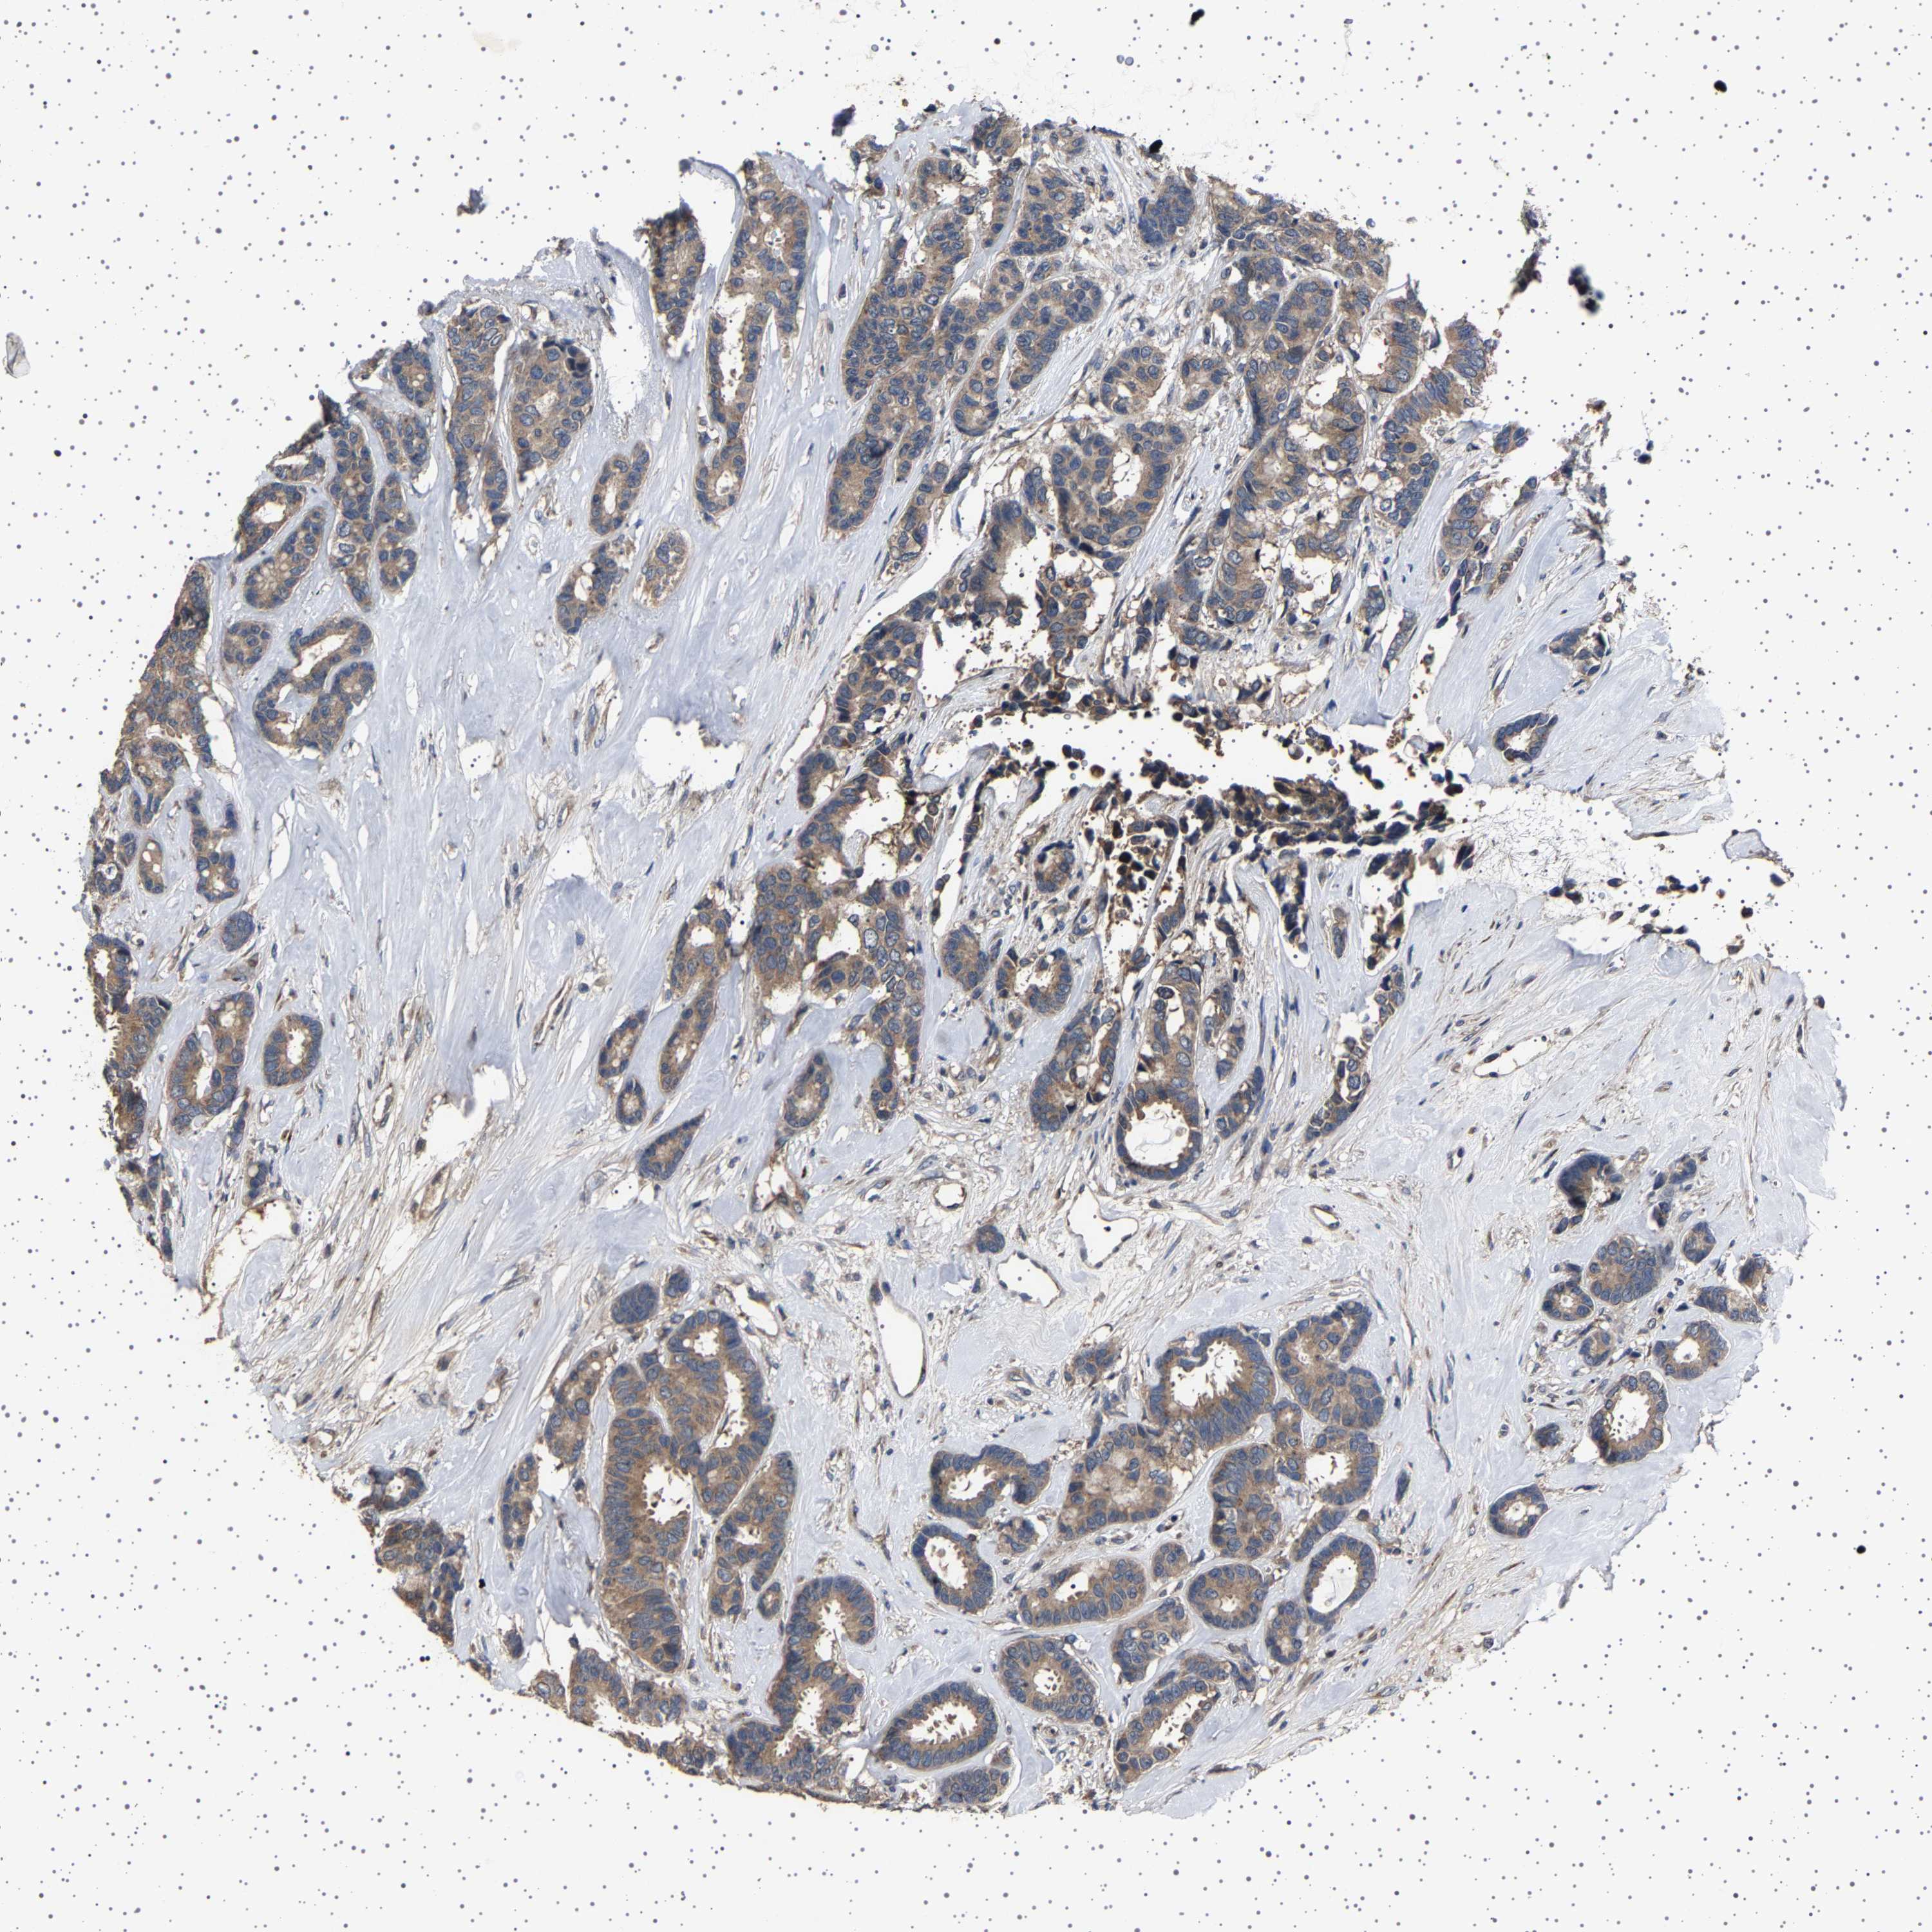

CANCER BREAST CANCER Show tissue menu

BRCA TCGA BRCA VALIDATION PROTEIN EXPRESSION